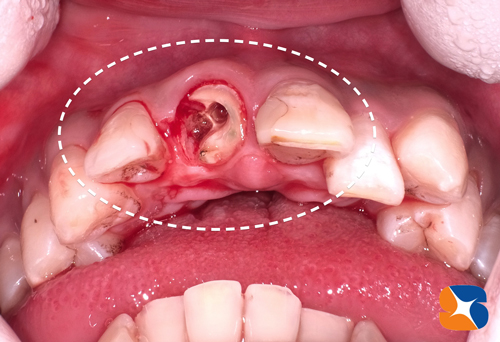

寝屋川市から40代の女性。主訴は「入れ歯で苦労している。医療従事者でしゃべる仕事をしている。上顎の骨が薄くて浅いのでインプラントは難しいと言われ続けてきた。先生の御意見をお聞かせ下さい。」

CTを使って骨の状態(骨の厚みと高さ)をチェックすると、厚みも高さもかなり不足していましたので、インプラント治療をするのなら人工的に骨を増強する必要がありました。また、黄色の点線の歯は、乳歯のようにグラグラしているので、抜歯をして当日その痕にインプラントを移植することもお伝えしました。

この画像は、ほお骨の横から人工骨を入れた所に、インプラントを植立したところです。

約4時間に及ぶ施術が終わりました。

〈内容〉

•抜歯2本→抜歯痕にインプラントを2本移植

•2㍉幅のほお骨の横から穴を開けて人工骨を増強する手術(サイナンスリフト)

•7連結の仮歯をセットして帰っていただく。

※静脈鎮静法を使って、リラックスした状態で施術を受けてもらっています。

※採血をして再生療法医療(CGF、AFG)を行い、人工骨の安定を図りました。